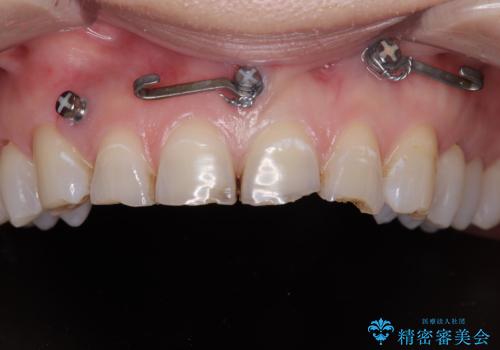

- 転んで欠けてしまった前歯を治したいと来院された患者様です。

この機会に、白くきれいにしたいとの事でした。

まず仮歯に置き換え、最終的な被せものの前に仮歯で形などを調整します。